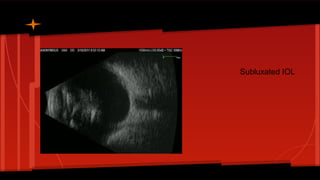

Subluxated IOL